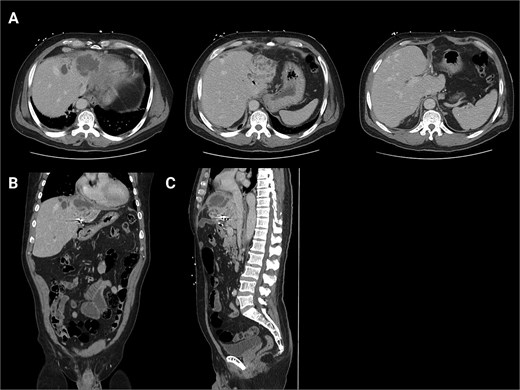

The patient presented the following day with fevers and new chest pain. He underwent a computed tomography angiography (CTA) chest and abdomen/pelvis, which revealed a left lower lobe consolidation and a moderate pericardial effusion. His hepatic abscess had increased in size to 7.2 × 5.5 cm (Fig. 2). Cardiology was consulted, and a bedside echo was performed, which found acute pericarditis. He was admitted and started on IV antibiotics and colchicine for his pericarditis. GI subsequently performed an ERCP, which showed no biliary or anastomotic stricture (Fig. 3). It was thought that it was likely a choledochal cyst, and the plan was for elective left hepatectomy. He was transitioned to oral antibiotics and discharged with colchicine for 3 months.

First readmission CT scans. (A) CTA chest images in the axial and sagittal planes illustrating the newly developed pericardial effusion. (B) CTA abdomen/pelvis images in the axial, coronal, and sagittal planes. These illustrate the abscess increasing in size.